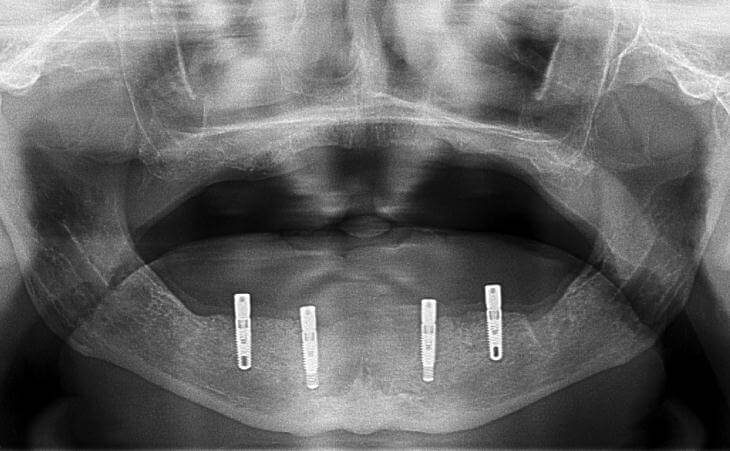

This is a 70 year old male who was unhappy with the fit of his lower denture. I placed 4 dental implants to anchor the denture and the patient was very comfortable.